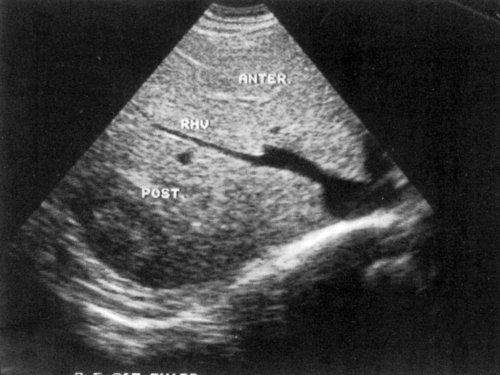

Размеры печени у взрослого человека могут варьироваться в зависимости от его роста и веса. Но в среднем, размеры печени у взрослого человека составляют примерно 15-20 см в длину, 7-10 см в ширину и 5-7 см в толщину.